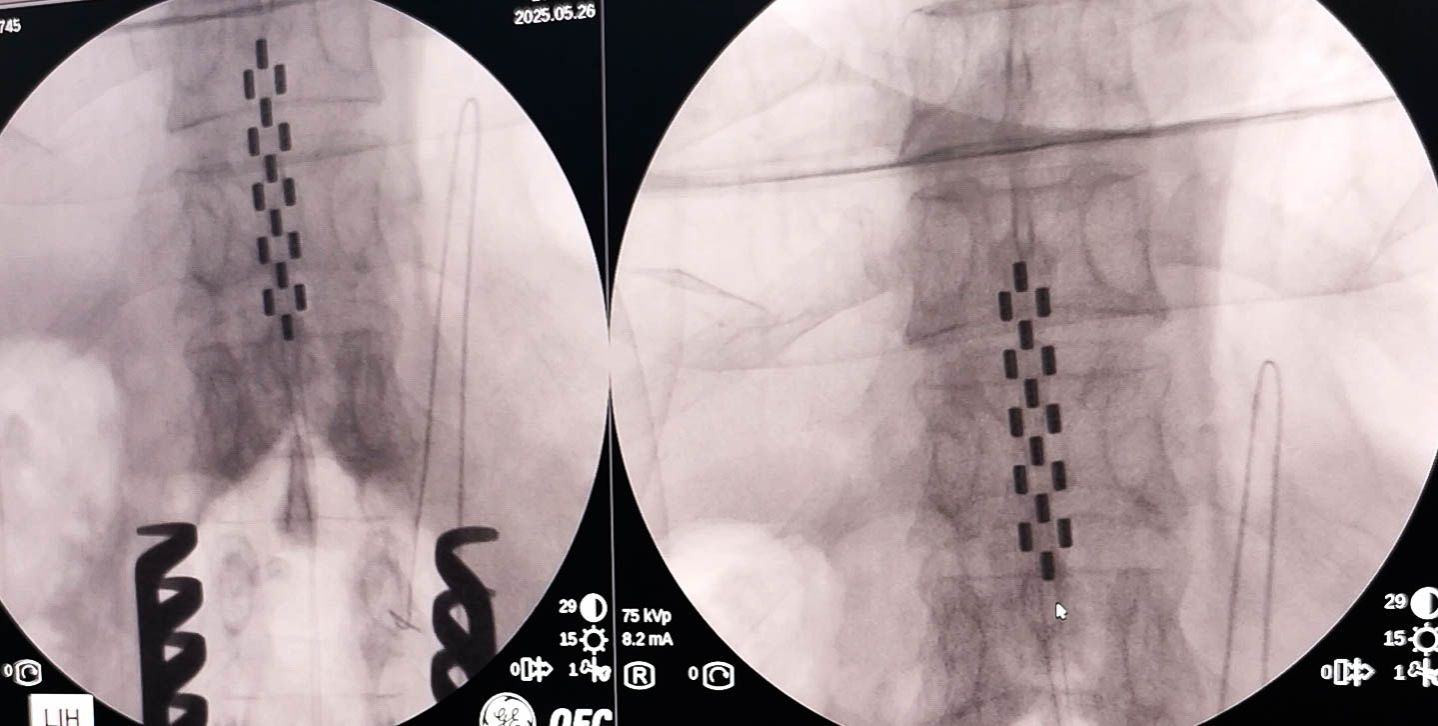

患者王先生(化名),4年前因脑出血导致左侧肢体偏瘫,虽经长期康复治疗,仍存在肢体僵硬、脚趾向下扣等症状,日常生活十分困难。在了解到脊髓电刺激术后,他来到西安交大二附院求诊。经过手术前缜密的评估,神经外科张熙副主任医师团队通过一个小切口,将电极植入到下胸段脊髓硬膜外的位置,术中通过拍X片确定电极位置良好,术中电刺激表明下肢肌肉反应良好。术后,王先生左脚趾内扣感觉消失,下肢较前轻松。待伤口愈合后,可进一步进行康复治疗。